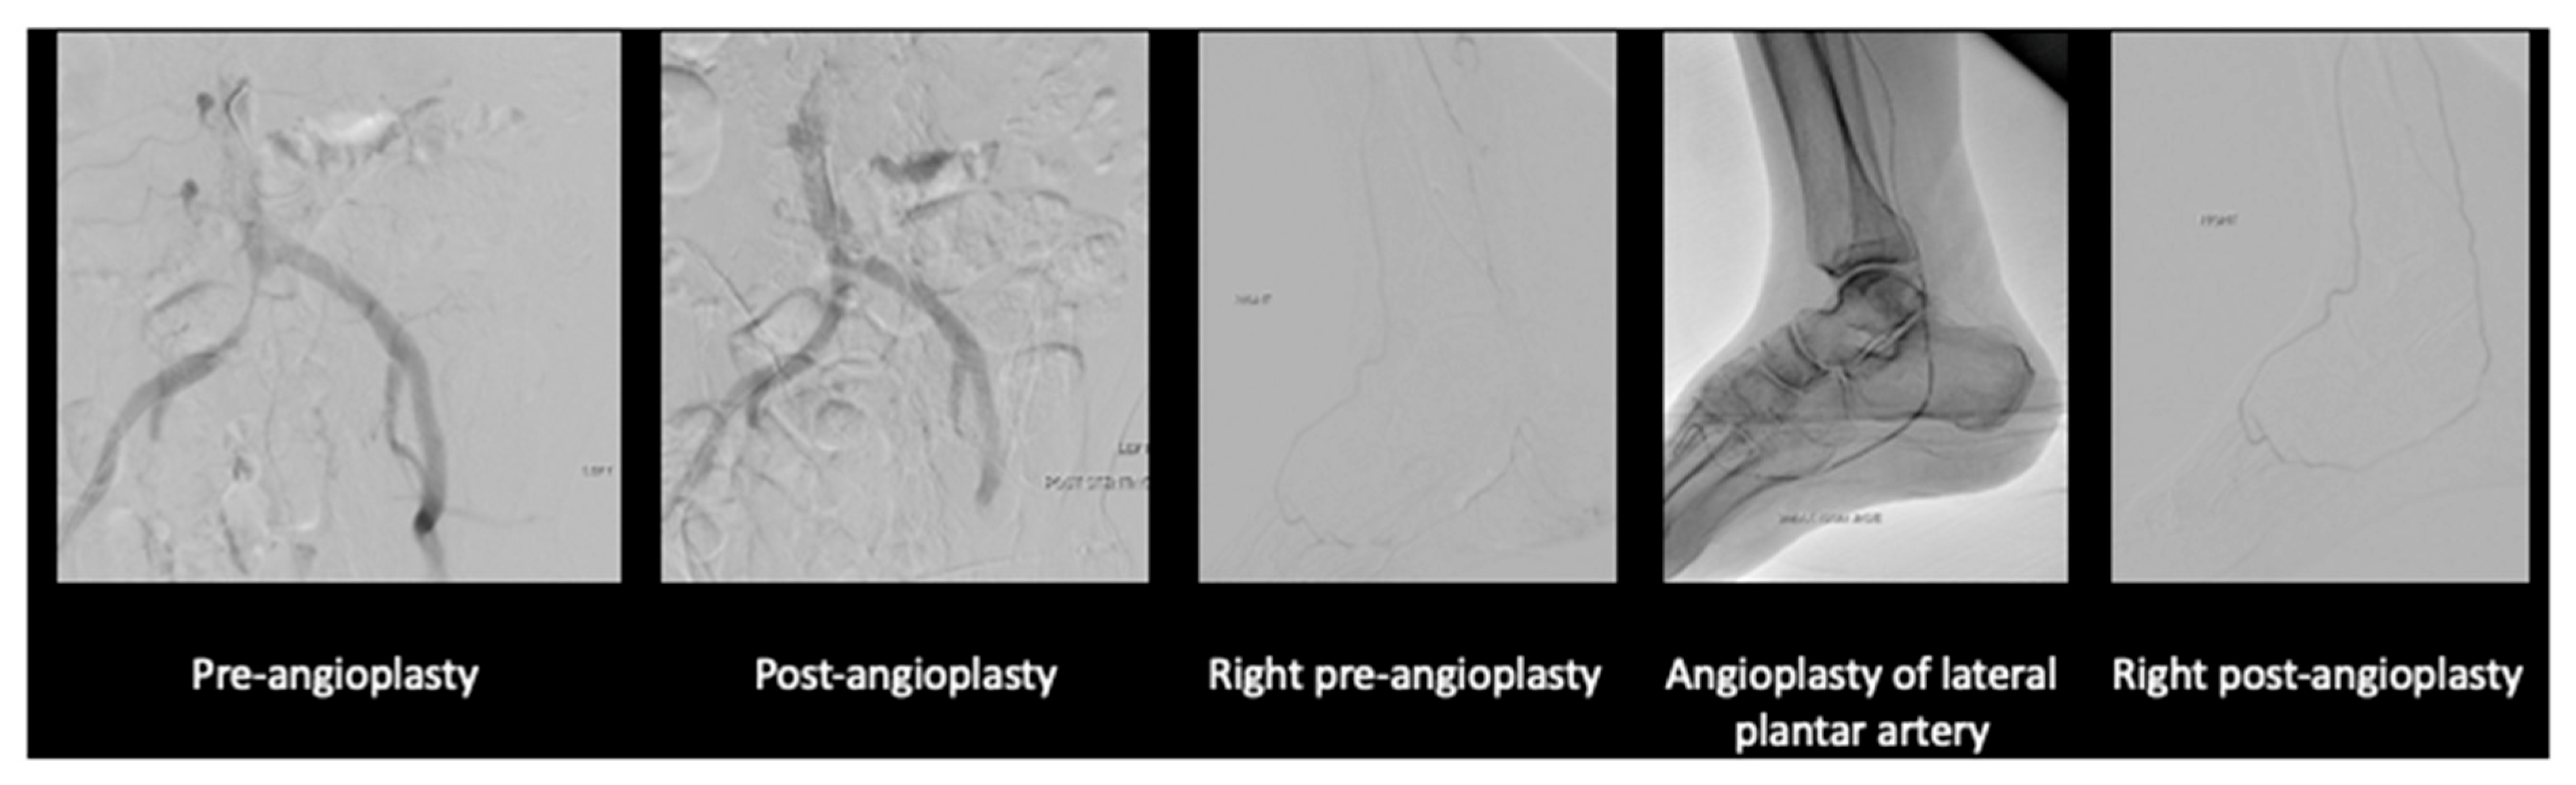

After much discussion, the patient and vascular team decided to attempt limb salvage with bilateral lower limb angioplasties and fifth toe ray amputations at the same setting. On the left lower limb, angioplasty to the anterior and posterior tibial artery was performed (Figure 3).

On the right lower limb, angioplasty to anterior tibial artery, posterior tibial artery, dorsalis pedis, and common plantar artery was performed (Figure 4).

Figure 3. Angioplasty images of the left lower limb.

Jcm 14 01642 g003

Figure 4. Angioplasty images of the right lower limb.

Jcm 14 01642 g004